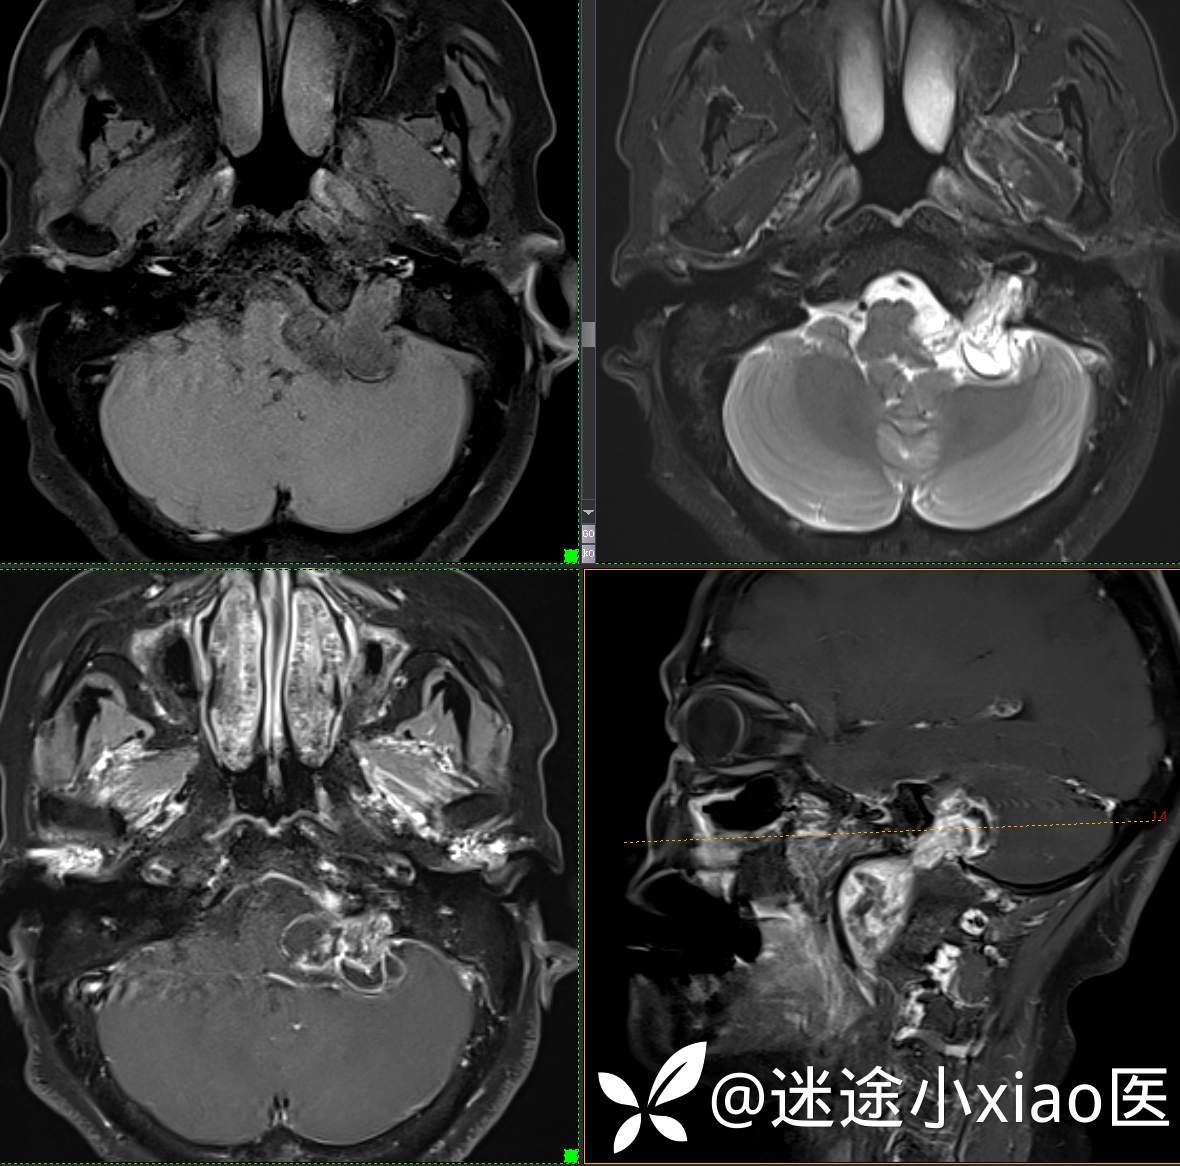

头颈组17:颈静脉孔区占位,副神经节瘤?神经鞘瘤?脑膜瘤?

患者性别:女

患者年龄:57岁

主 诉:  声音嘶哑进食困难伴左侧颌部麻木半年

现病史:  【患者半年前无明显诱因出现声音嘶哑,进食困难,只能进食糊状食物,伴有恶心呕吐,无明显头痛头晕,未加重视。